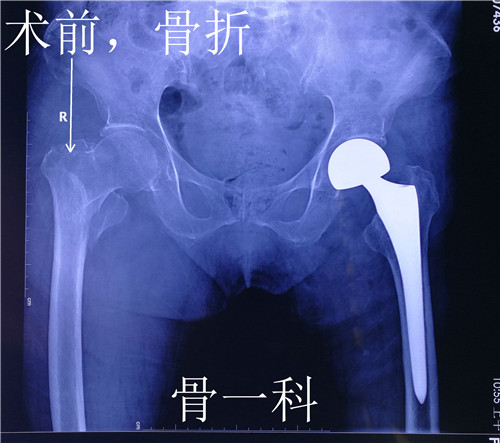

据了解,来自渭南市临渭区的郑老太太,年近92岁。9个月前因外伤导致左股骨颈骨折,骨一科为她实施了左侧人工股骨头置换术,术后老人恢复良好,一直在西安女儿家生活。这次老人散步时又不慎摔伤,当即感觉右髋部疼痛,无法站立行走,随后亲属将她送到就近的西安一家医院就诊。在医院拍右髋部x线检查显示,老人右股骨粗隆间骨折粉碎性骨折。该院让她住院手术治疗,她坚决要回渭南在骨一科治疗。

骨一科翁主任和全科医生对老人病情进行了评估和讨论,由于老人是高龄患者,除了右侧股骨粗隆间骨折,之前左侧还做过人工股骨头置换术,并且有骨质疏松症、高血压病、糖尿病Ⅱ型,手术风险和麻醉风险都特别大。在麻醉科李万鹏副主任和徐巧玲主任医师的协助下,骨一科为老人实施了右股骨骨折闭合复位髓内针内固定术,手术非常成功。此手术面对老年髋部股骨粗隆间骨折的特殊人群,优点是减少出血、缩短手术时间、减少创伤、减少麻醉时间,极大降低手术风险。